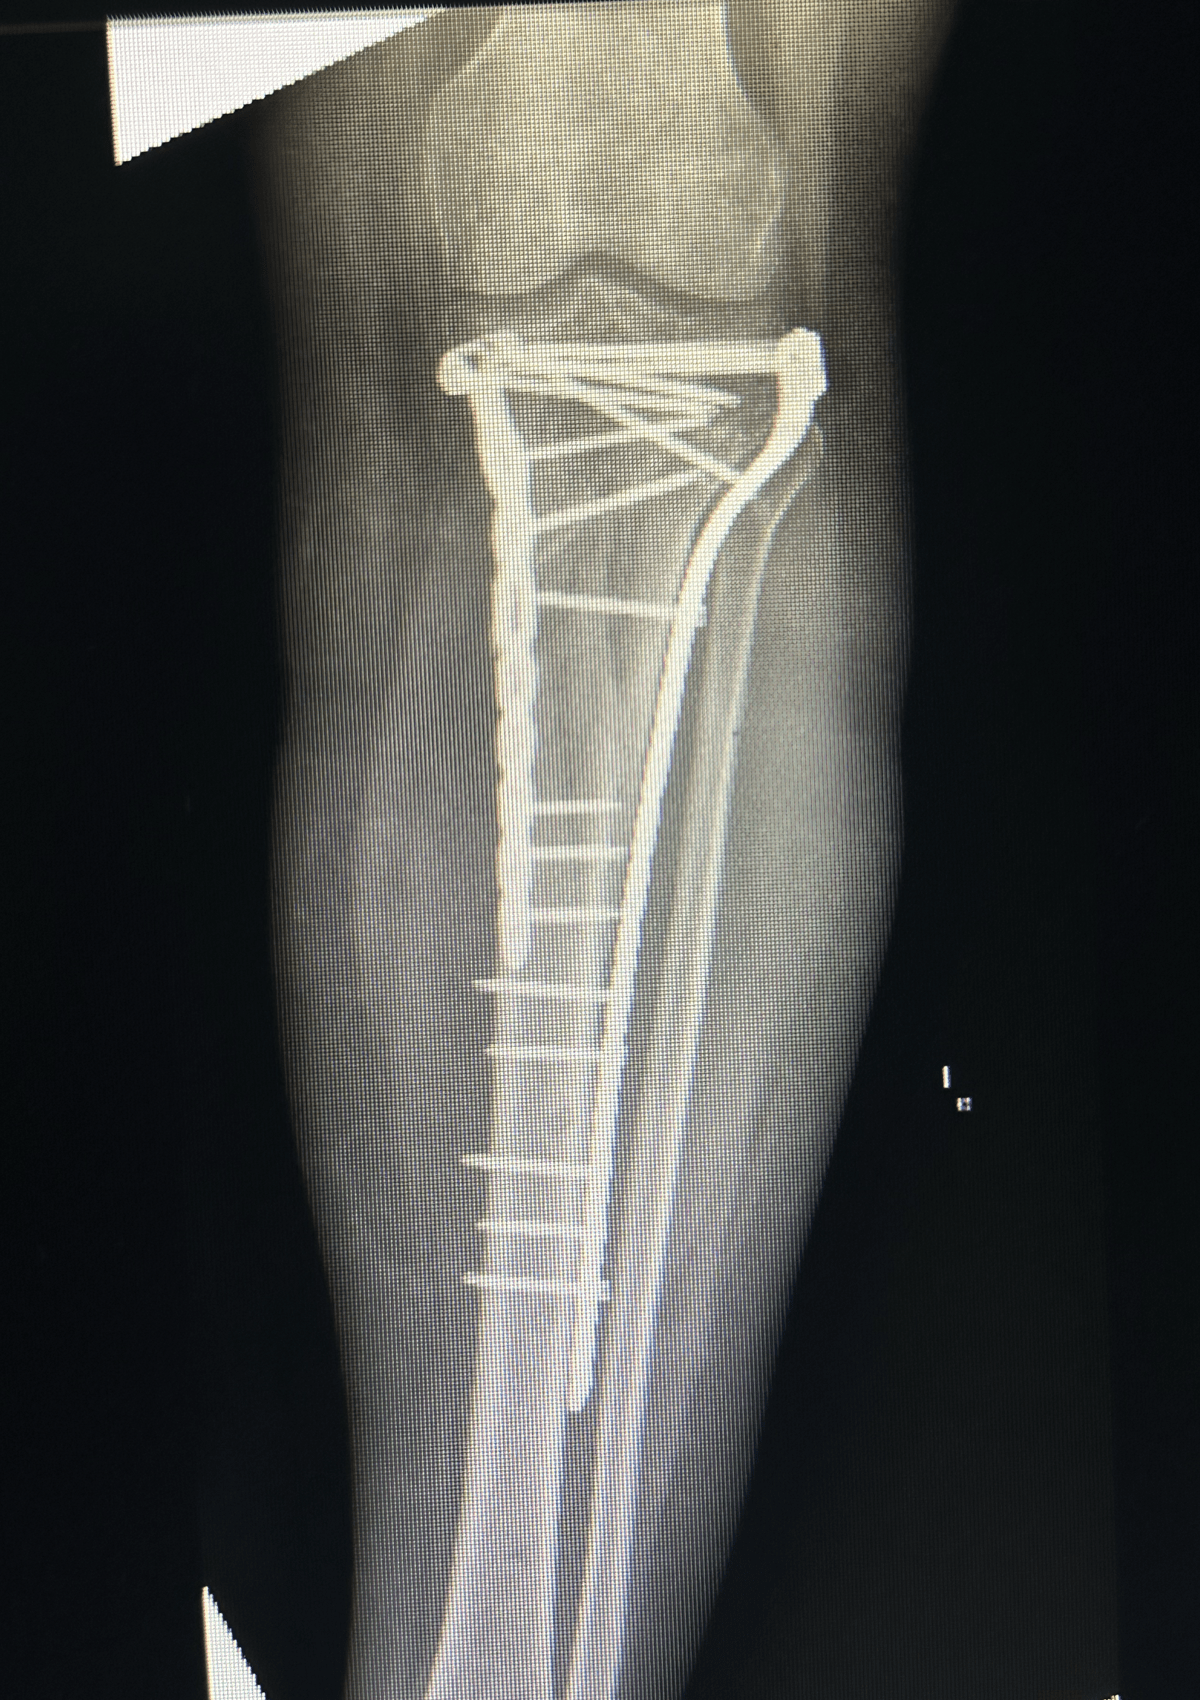

Before & After